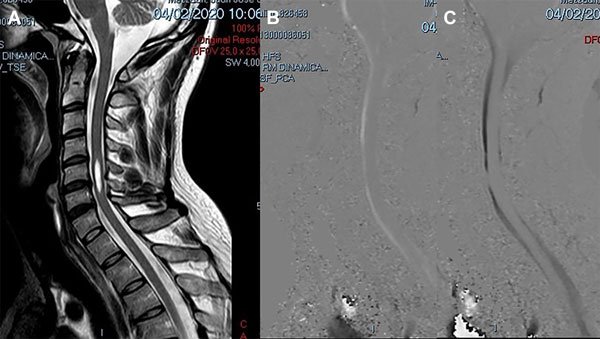

Caso 4: Diagnóstico diferencial

Un varón de 38 años de edad consultó por haber padecido una cérvico braquialgia derecha 30 días antes. En el momento de la consulta sus síntomas habían desaparecido y el examen neurológico fue normal. La RM mostró discopatías cervicales múltiples con una dilatación quística en la médula cervical a nivel C5-C6 que no tomaba el contraste con gadolinio (Figura 6A). Para profundizar el diagnóstico diferencial se realizó una RM en contraste de fase para medir la velocidad del LCR a nivel del canal cervical. La velocidad medida fue de 11 cm/seg (Figura 6B-C). Se hizo el diagnóstico de SM espinal primaria causada por una discopatía cervical a nivel C5-C6. Como el paciente estaba asintomático sólo se indicó control periódico. En su última evaluación, 2 años después, la situación clínica e imagenológica no había cambiado por lo que se mantuvo la misma conducta.

Figura 6: Caso 4. A: RM de columna cervical en plano sagital ponderada en T2 que muestra una cavidad intramedular entre C5 y C6 compatible con siringomielia. B: Estudio de dinámica de LCR que muestra una imagen de magnitud en fase anterógrada con señal hiperintensa el flujo en sístole con disminución del pasaje del LCR en C5-C6. C: Estudio de dinámica de LCR que muestra una imagen de magnitud en fase retrógrada con señal hipointensa el flujo en diástole con la alteración del pasaje de LCR a nivel C5-C6.